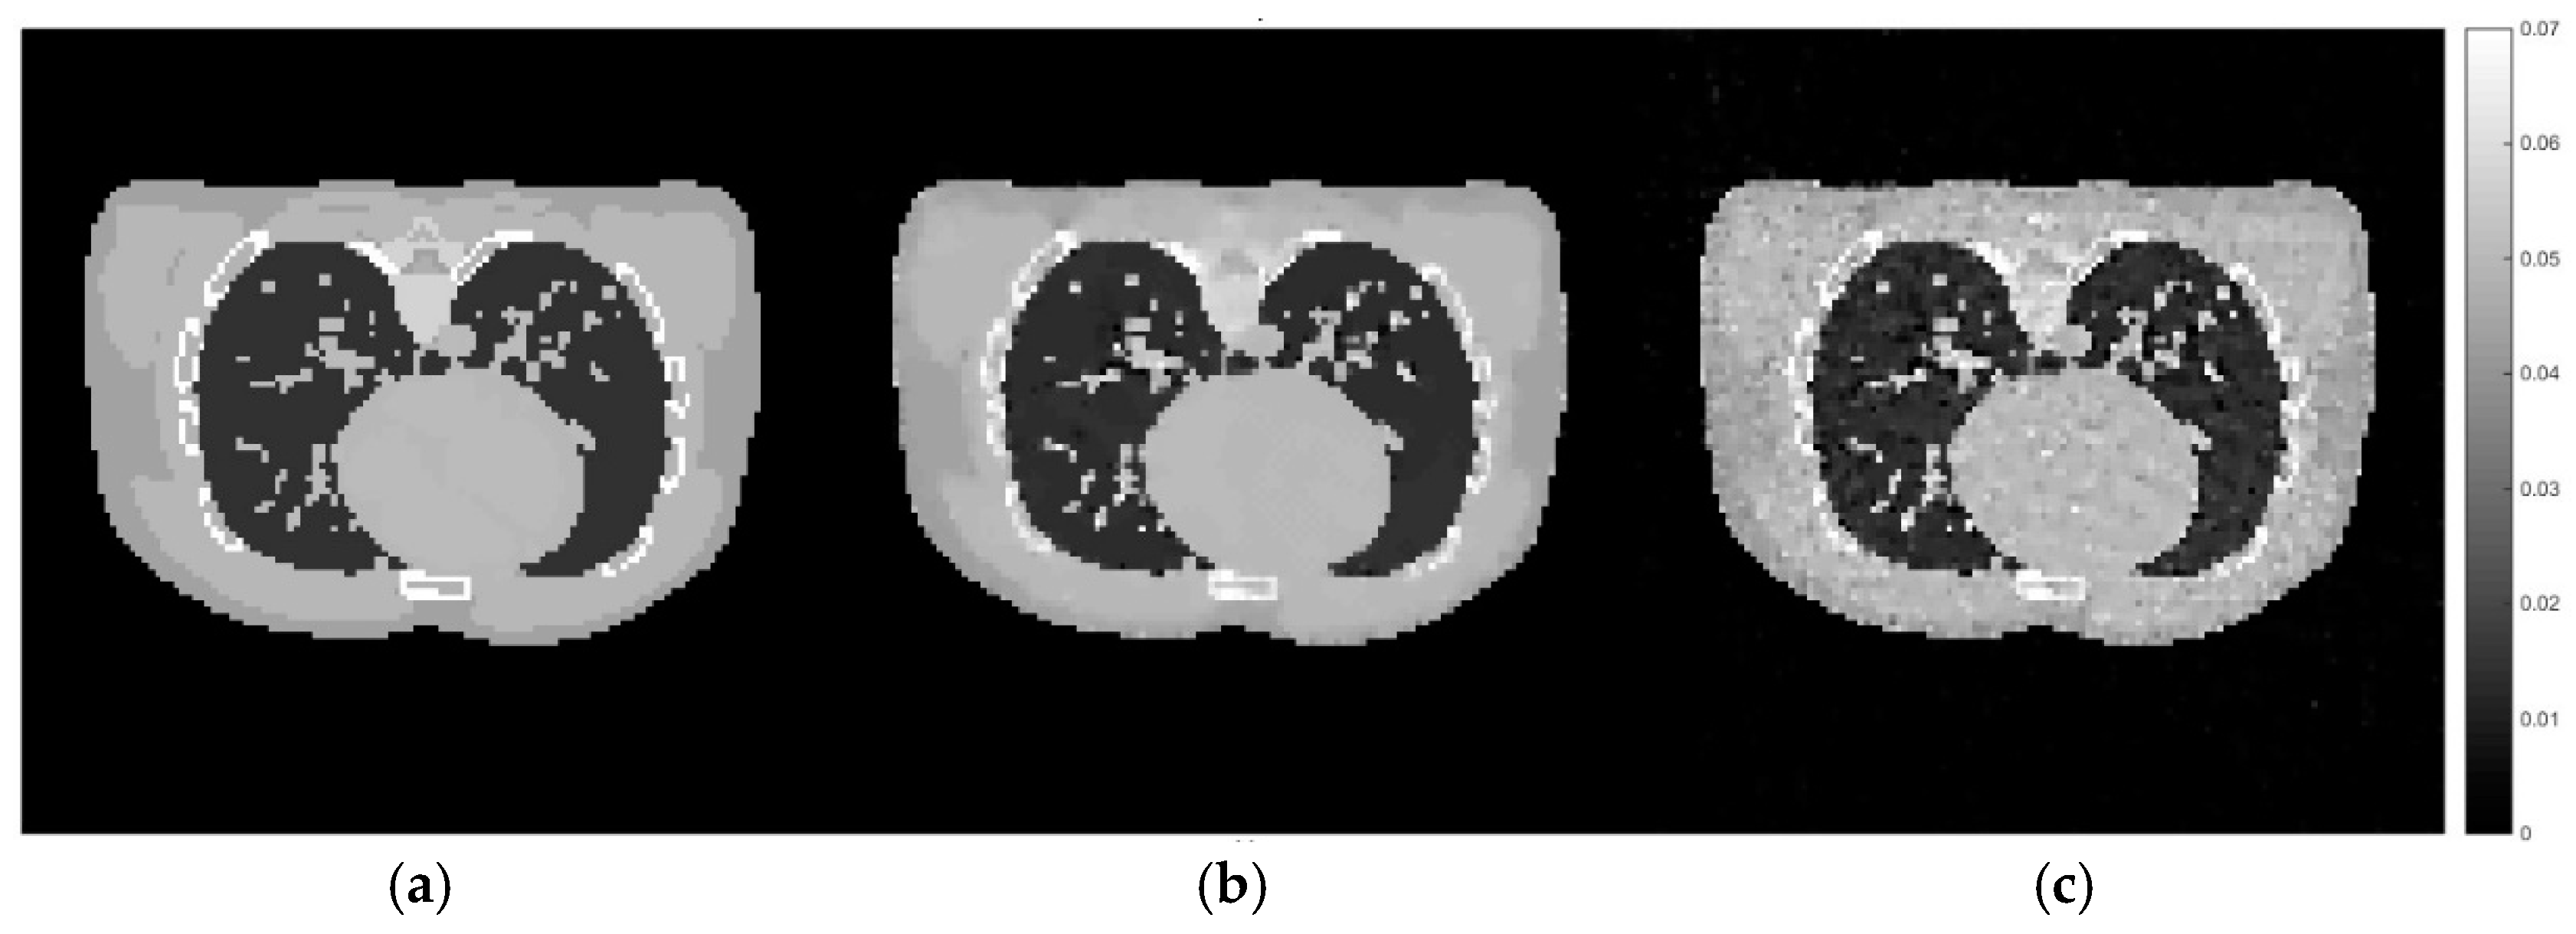

According to Figure 11, the reconstruction using the set of hyperparameters obtained from the training dataset still able to produce good quality of image, comparing to other methods. We then implement the proposed method directly to the projection simulated from the male phantom to further analyse the difference between these two cases. The cross-sectional slices are shown in Figure 12. The relative errors and the UQI, as well as the sets of hyperparameters used in each method are presented in Table 5.

Figure 12.

Cross-sectional slices of (a) the exact image of male phantom data, (b) the reconstruction from directly implemented the proposed method on the male phantom data, (c) the reconstruction using the hyperparameters obtained from the training stage.

According to Figure 12 and Table 5, it can be concluded that the set of hyperparameters obtained from the proposed algorithm with the training set can be applied to different imaging samples and produce a result which is superior to CGLS and TV with arbitrary parameters. However, the set of hyperparameters obtained from directly implementing the proposed algorithm with the male phantom projection shows even better results. This experiment proves that the selection of hyperparameter for the TV regularisation algorithm, specifically for the AwPCSD algorithm, is data-specific. The optimal set of hyperparameters from one training dataset can still be applied to different image sampling within a similar context. However, the optimal result might not yet be achieved. It is significant to fine-tune the hyperparameters, in order to obtain the optimal result for a given data. This is the advantage that the proposed algorithm offers, to avoid the tedious process of manual hyperparameter tuning. The same pattern of experiment is performed on the female phantom and the results, as presented in the Figure 13 and Figure 14 and Table 6, confirm the conclusion stated above.